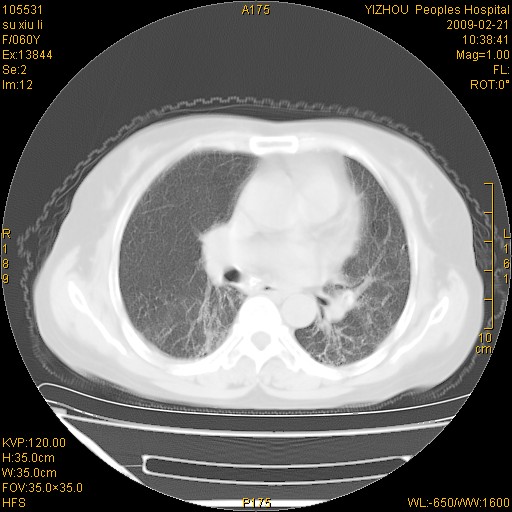

标题: CT18259:两肺间质纤维化? [打印本页]

标题: CT18259:两肺间质纤维化?

女,60岁,反复咳嗽1月。

两肺支扩,以肺为著合并双肺较广范纤维化病变。建议除外结核等病变。

间质性肺炎

符合间质感染,部分纤维化表现

特发性间质纤维化

特发性间质纤维化伴支扩!